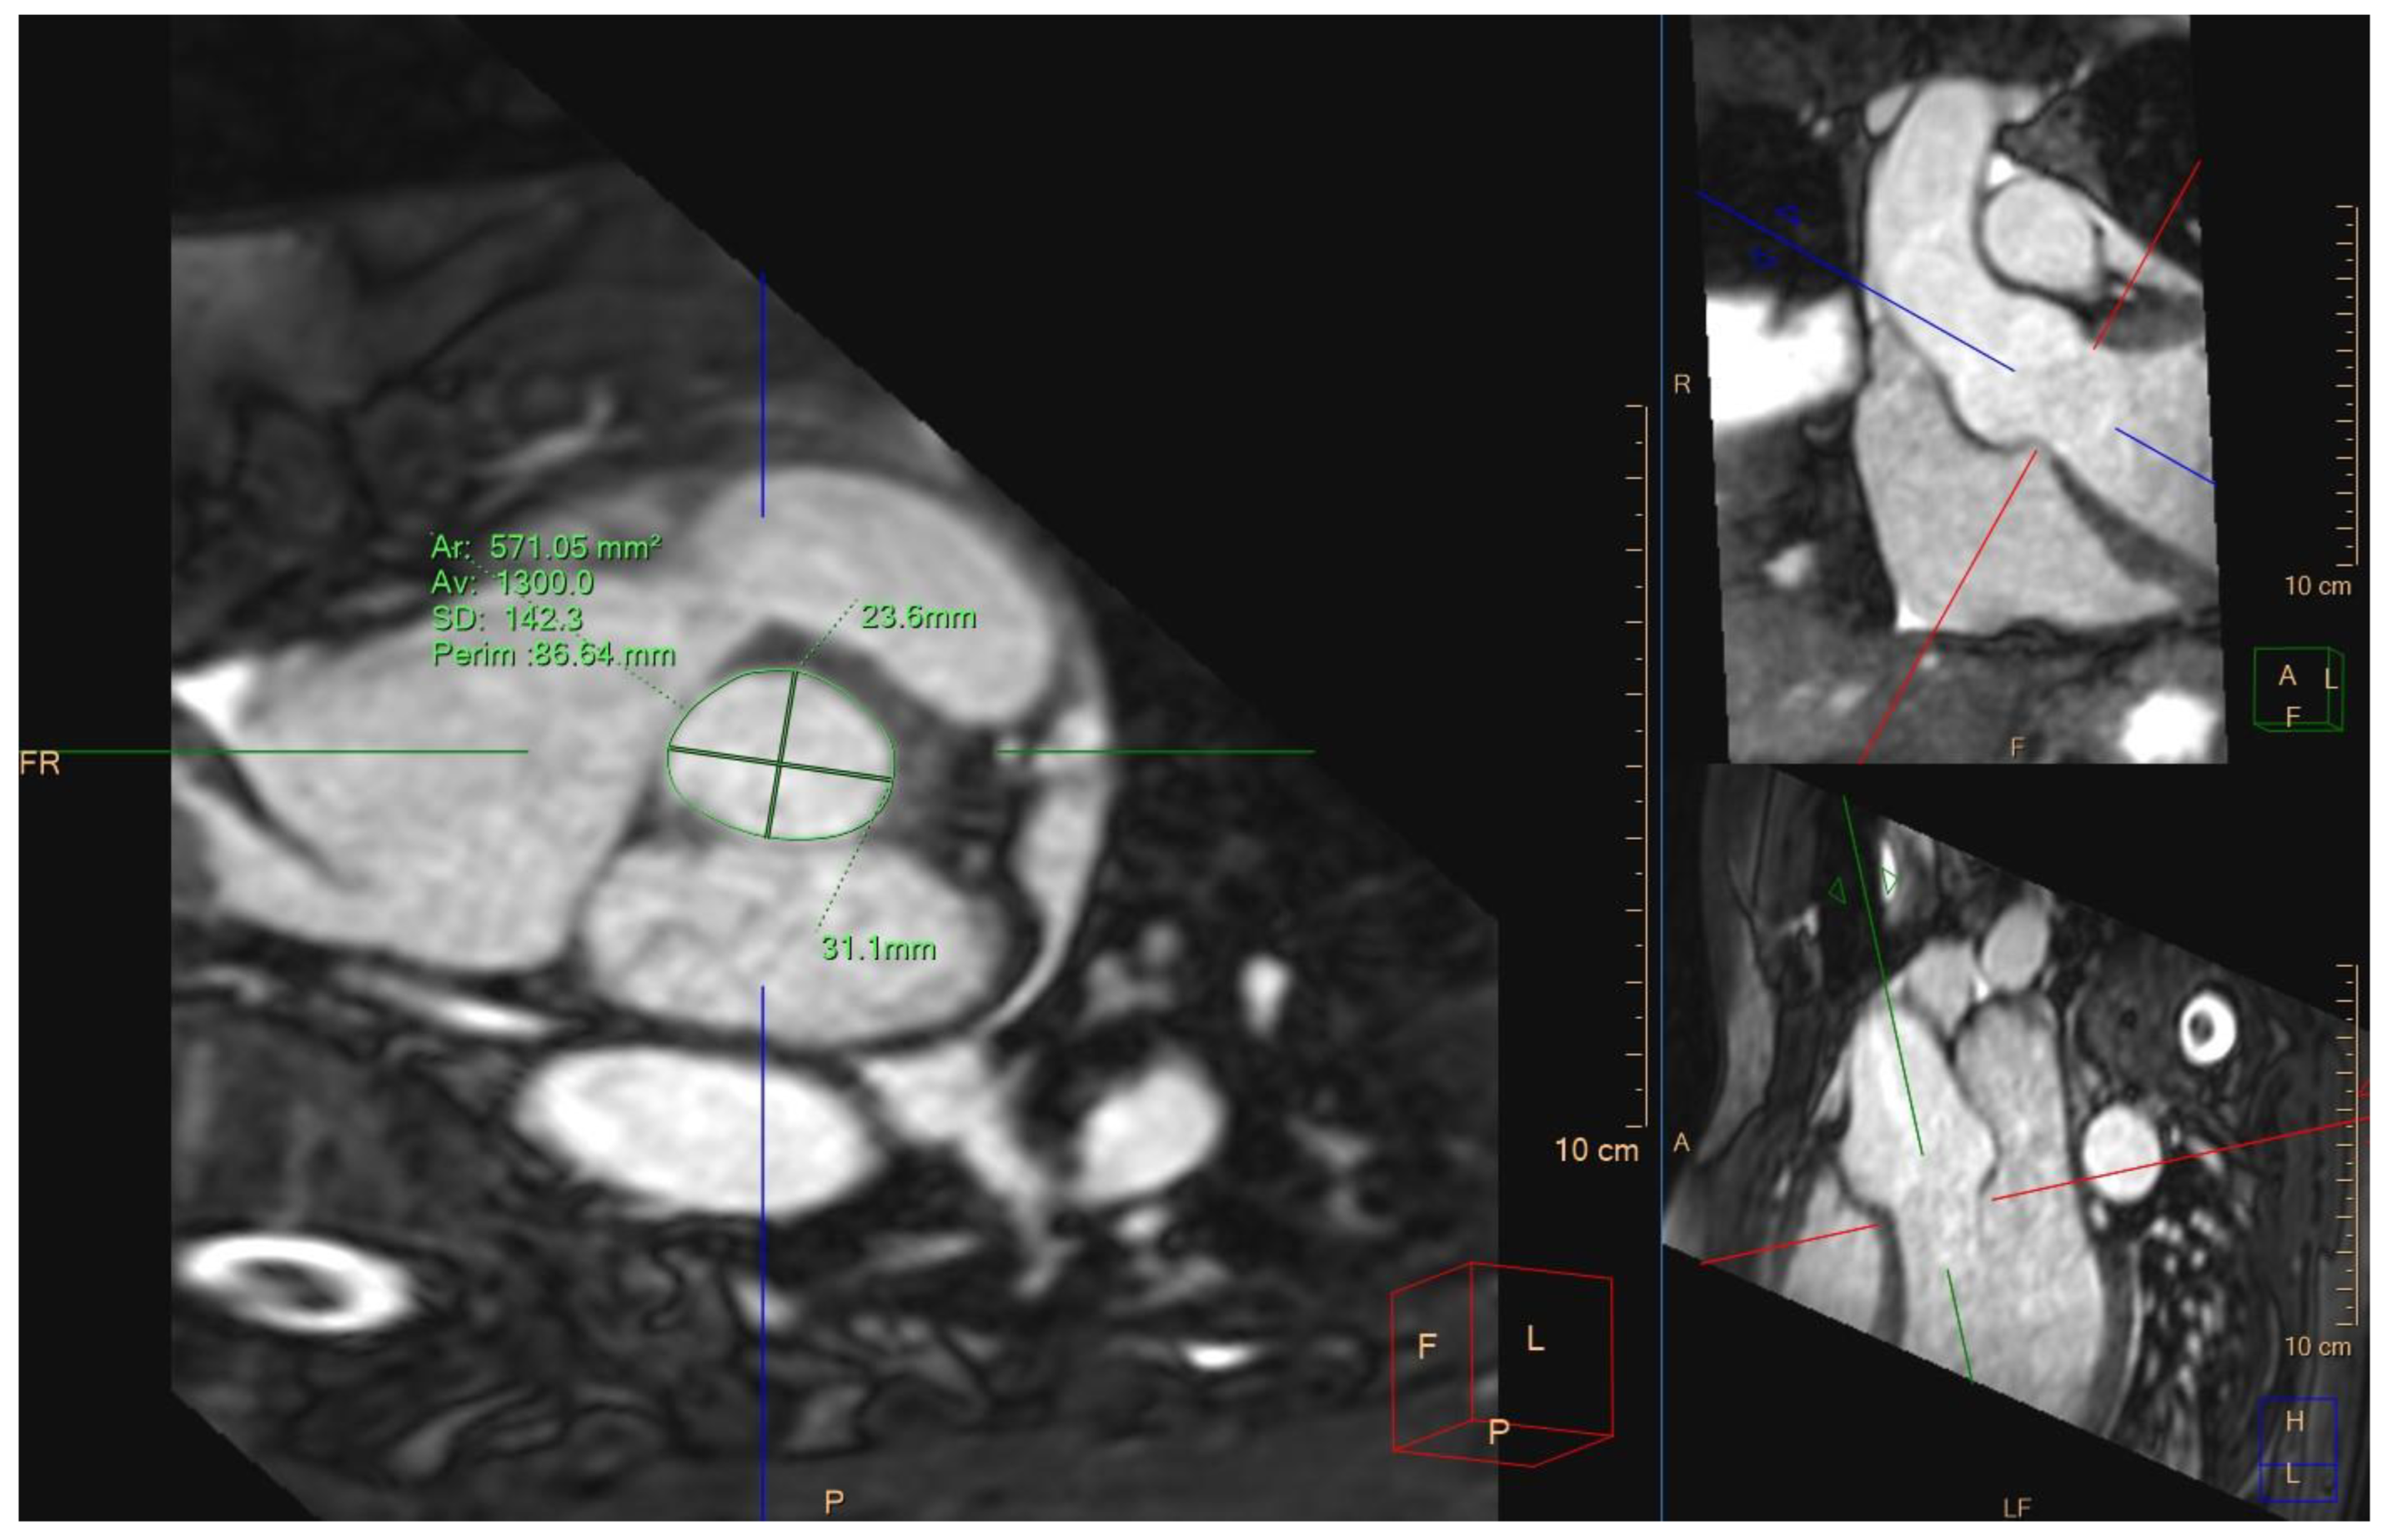

The EACVI Textbook of Cardiovascular Magnetic Resonance (The。4D-Flow Cardiovascular Magnetic Resonance Sequence for。Cardiovascular magnetic resonance physics for clinicians。在庫整理に伴う、出品です。表紙:きれい中身:きれい商品の状態は、中身の状態です梱包:緩衝剤リサイクル利用大型本の為、宅急便での発送となります。4D Flow cardiovascular magnetic resonance consensus。古いものですので時間経過によるシミ等についてはご理解下さい。J.M. Coetzee & Paul Auster 洋書セット。ストレンジャーシングス イレブン役 ミリー ボビー ブラウン 直筆サイン本。#洋書ぐぐ